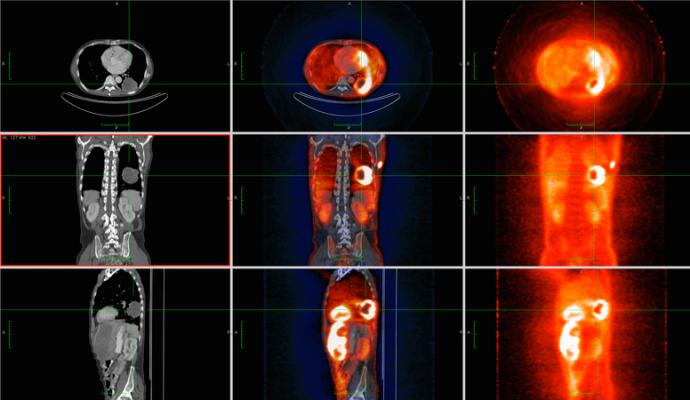

The Philogen Group has a Phase I clinical trial (called FAPrimo) underway in Europe to evaluate the safety and dosimetry of 68Ga-OncoFAP in patients with solid tumors. The study is planned to enroll up to 20 patients who will undergo PET/CT imaging with 68Ga-OncoFAP. The first three enrolled patients in the trial were imaged in November 2023 at the National Cancer Institute of Milan (INT). To date, 68Ga-OncoFAP-DOTAGA has been used for PET imaging applications in approximately 100 patients with various solid tumors through Philochem’s collaboration with the University of Münster, Germany.

“We are delighted to announce this key milestone of the first three patients being dosed in the Phase 1 trial for 68Ga-OncoFAP PET in the detection and localization of advanced solid tumors,” commented David Gauden, D.Phil., Chief Executive Officer of Blue Earth Diagnostics. “68Ga-OncoFAP is an innovative and promising addition to Blue Earth Diagnostics’ robust portfolio of precision PET radiopharmaceuticals. We are grateful for the support of our parent company, Bracco Imaging, S.p.A., in helping to advance innovation to shape the future of precision medicine and improve patients’ lives worldwide with imaging technology such as OncoFAP. Based on preclinical studies and early clinical experience, 68Ga-OncoFAP has demonstrated favorable radiochemical properties, rapid clearance from organs and soft tissues and avid tumor uptake. We look forward to continuing collaboration with Philochem throughout this Phase 1 trial and applying our deep expertise in radiopharmaceutical development and commercialization as we advance further, with the goal to help patients and address unmet needs in cancer.”

Radiolabeled FAP ligands have demonstrated high binding affinity, rapid binding to FAP-expressing tumors and impressive lesion to background ratios in patients with a broad range of cancer types. They can be labeled with isotopes such as 68Ga or 18F for diagnostic PET imaging, or with therapeutic radioisotopes such as 177Lu or 225Ac for therapy.